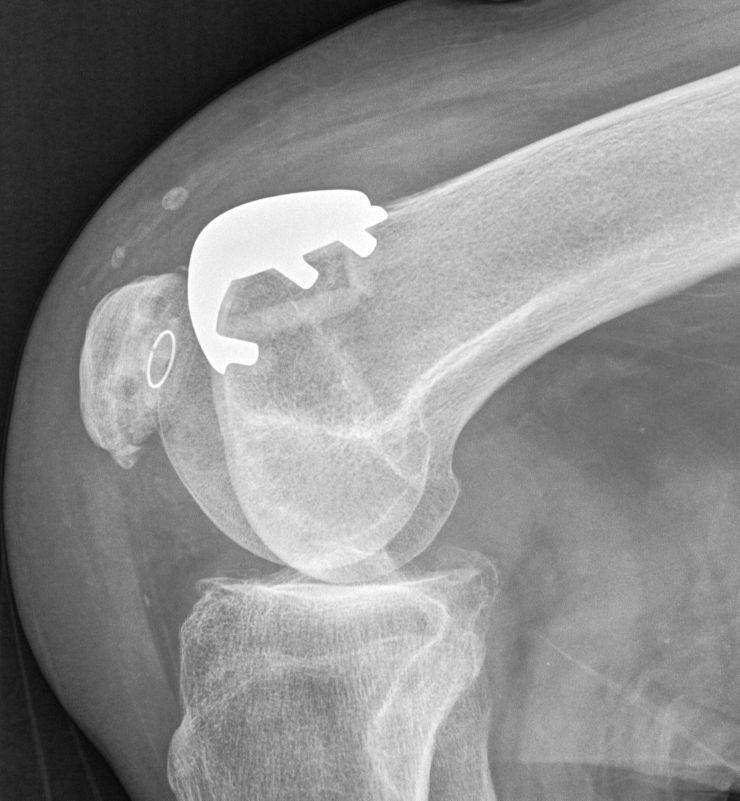

如果不小心步入晚期后,患者的疼痛只会更加强烈,此时患者只要产生运动,膝关节就会传来剧烈的疼痛,而且骨赘的增大还会影响患者膝关节的活动度。到这时,医生会建议你手术消除骨赘,或者采用髌骨关节置换手术一劳永逸。